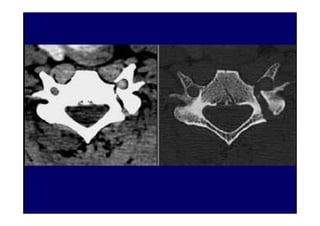

• 2. Tomografia Computadorizada

Está indicada no estudo de doenças ósseas,

sendo imagens que revelam espondilose e

osteófitos nas articulações zigoapofisárias.

É útil para medida do canal vertebral e o

forame de conjugação.

Observam-se imagens patológicas em

pacientes assintomáticos .